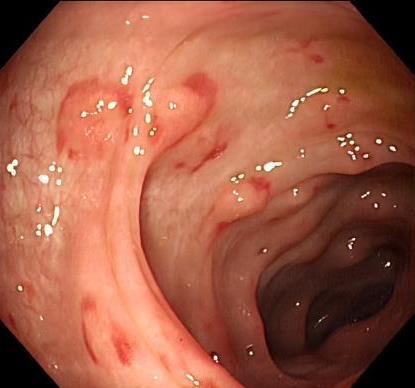

• 获得性免疫缺陷综合征合并马尔尼菲篮状菌导致肠道感染的内镜下表现(附6例报告)

2026, 32(3):84-88. DOI: 10.12235/E20250461

摘要 (32) HTML (27) PDF 3.50 M (26) 评论 (0) 收藏

摘要:目的 探讨获得性免疫缺陷综合征(AIDS)合并马尔尼菲篮状菌(TM)感染导致肠道感染的内镜下特征。方法 回顾性分析2022年11月-2024年10月于该院确诊为AIDS合并TM感染导致肠道感染的6例患者的临床资料。包括:临床症状、实验室检查、影像学检查、内镜检查和病理检查等。结果 6例患者中,男5例,女1例;发病年龄26~67岁;AIDS合并TM感染导致肠道感染患者的临床表现为:腹泻、腹痛、腹胀和恶心呕吐。其中,2例有消化道出血表现。实验室检查:6例患者外周血白细胞计数为(1.37~4.49)×109/L,血红蛋白计数为(67~99)g/L;CD4+T淋巴细胞为(1~52)个/μL,CD8+ T淋巴细胞为(61~321)个/μL,CD4+T淋巴细胞/CD8+T淋巴细胞比值为(0.01~0.18)。6例患者均行HIV RNA检测。其中,5例HIV RNA阳性。血培养:可见丝状真菌,报告显示为TM。影像学检查:6例患者CT结果可见肠系膜及腹膜后多发淋巴结肿大。内镜检查:6例患者内镜下均可见肠道病变。其中,十二指肠糜烂溃疡2例,结肠多发糜烂溃疡4例。病理检查:6例患者幽门螺杆菌(Hp)结果均为阴性,黏膜下可见成簇的小球形真菌孢子,符合TM感染;特殊染色:PAS(+),六胺银染色(+)。结论 当AIDS晚期患者出现消化道症状时,应警惕TM感染,病变部位常见于全结肠和直肠,亦可累及十二指肠,内镜下表现多为溃疡、糜烂和隆起性病变,形态表现无特异性;及时行胃肠镜检查、病理活检、特殊染色和免疫组化是确诊的关键。